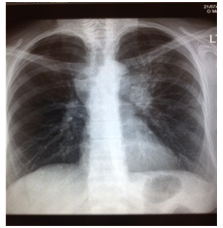

A subsequent Chest X-Ray (Figure 1). showed a left density and a preliminary diagnosis of pneumonia was given and antibiotics were started until further imaging was completed.

Figure 1 Chest X Ray illustrating left lung opacity.